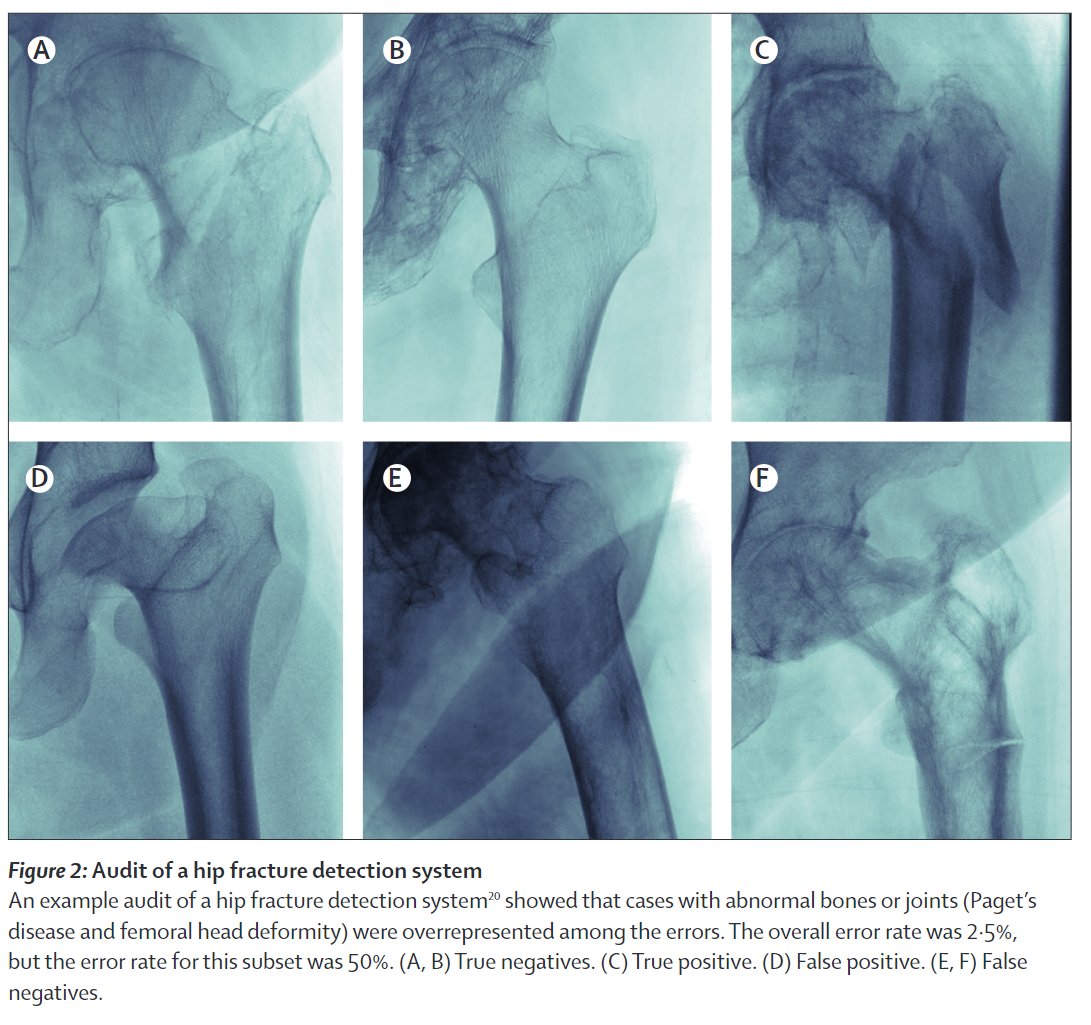

The high performance hip fracture model (AUC 0.994 vs 0.969 for radiologists) fails unexpectedly on an extremely obvious fracture and produces a cluster of errors in cases with abnormal bones (Paget's disease etc).

These findings (and risks) were only detected via audit.